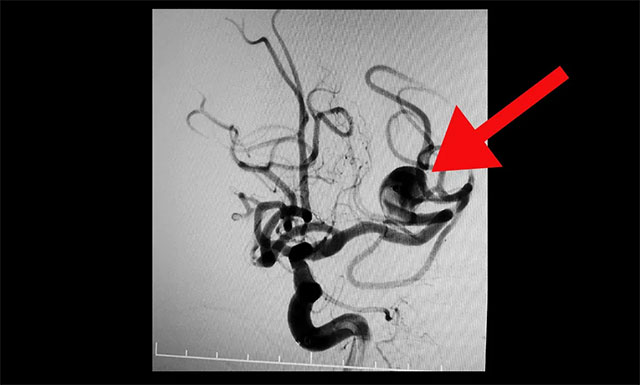

DSA检查确诊:左侧大脑中动脉分叉部动脉瘤,瘤颈 6mm,瘤体 13 mm* 15 mm,属于大型宽颈复杂动脉瘤。该动脉瘤有持续增大并有破裂风险,手术指征明确。

▲ DSA 检查确诊:左侧大脑中动脉分叉部动脉瘤